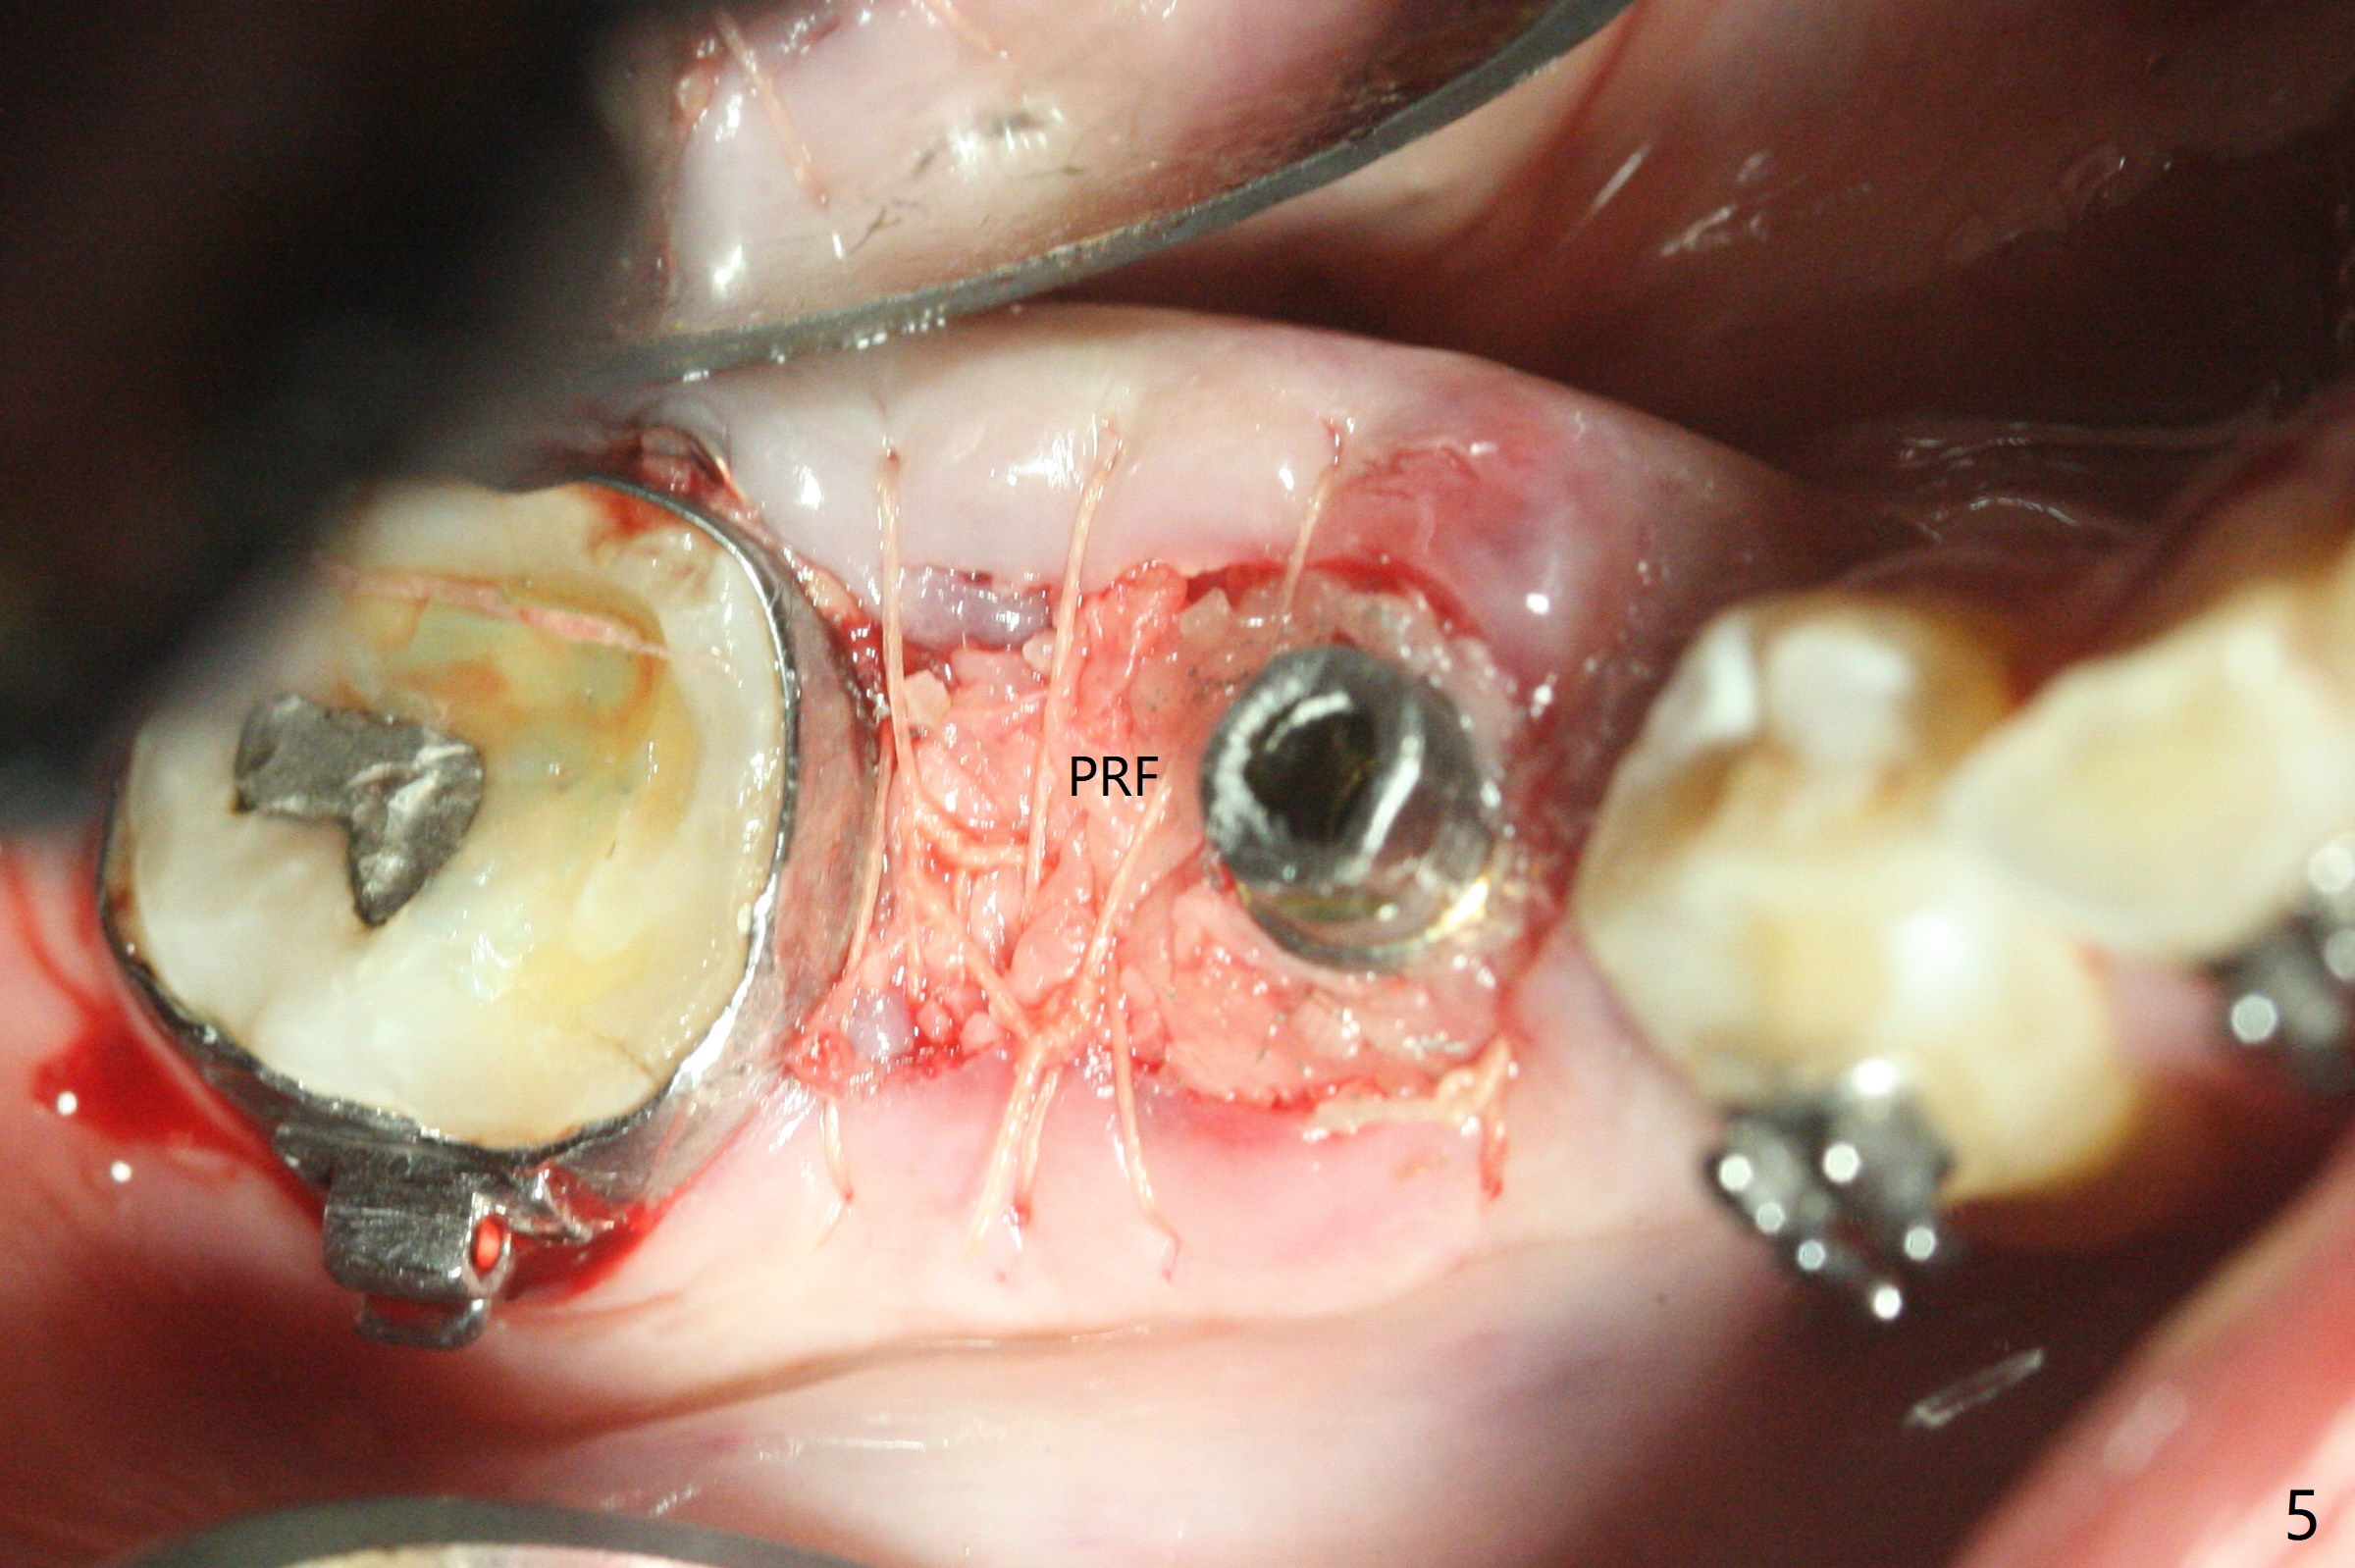

35岁男牙齿矫正后2年5个月右下6远中深龋,拔除后,近中根尖肉芽组织(图零(术前CT冠状切面):*)刮除疼痛,必须阻滞麻醉才能控制疼痛,可能与下牙槽神经分支(图零:红箭头)有关。原先准备在近中牙槽窝近中种植(5x11.5mm),术中发现近中牙槽窝种植好像方便,位置不错,不由自主在那里开始钻洞,由于牙槽窝深,钻洞必须13毫米(图一(接近神经:红虚线)),之后发现钻洞(图二(术前CT3D长轴切面(黑色:近中,远中牙槽窝)):红圆圈)不够理想,使用Lindamann Bur将钻洞往颊侧近中移动(图二:箭头),最终在这方面结果可以(图三,三’,四),虽然接近神经,术后没有神经麻痹。放置粘性骨粉(图四:*),PRF膜,4-0 PGA缝线(图五),最后使用树脂敷料(图六:A)。后牙垂直空间少,术后一周需要降低树脂敷料高度(图七)。术后一个月取出敷料,牙槽窝愈合,植体平台远中稍微暴露(图八),准备一个月后制作临时牙冠。术后两个月植体远中没有暴露,但是基台远中边缘太高了(图九:>),换成6x4毫米愈合基台。下个月换成袖短的修复性基台,安置临时牙冠,牵拉7。舌侧cleats之间放置power chains,颊侧power hooks。其实术后4个月安置临时牙冠和band(图十),牙冠牙合面加高,这样7可以无阻挡移动(图十一:*;16x22 arch wire)。7远中放置power hook行不通,因为末端碰到颊侧前庭牙龈,造成创伤。只好用7颊侧原有牵引勾,在6近中安置一个短的power post (? 图十:箭头),按常规post往下,之间放置12毫米closed spring。如果post往上安置,7牙根牵引可能更有效?近中牵引一个月,第二磨牙前移大约2毫米(图十二:^),稍微近中倾斜,closed spring从12毫米更换到9毫米,舌侧换新的power chains x 4。下一个预约,用sensor 1拍摄根尖片证实第二磨牙近中倾斜,然后在它远中16x22钢丝安放power hook,下缘向颊侧弯曲,避免接触接触粘膜。